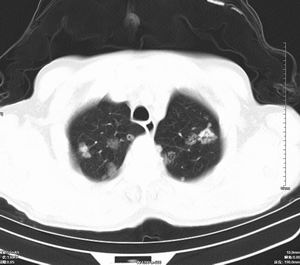

男 60岁,咳嗽,胸疼半年,请各位老师讨论.

肺内多发小结节,部分内见空泡,边界大部分清楚.多考虑:1 韦格氏肉芽肿.2 肺泡癌伴肺内转移不除外.

肺内多发结节样病灶,部分内见空泡影,边界大部分清楚,多考虑:

1.金葡菌感染

2 转移不除外

影像学表现:文献报告肺部浸润性见于50-65%的病人,肺部均有浸润,表现为肺内多发或单发结节影,出现多发厚壁空洞,内壁粗糙,易合并细菌性肺炎,也可出现胸腔积液。ct及hrct扫描可见大小不等的结节多分布于肺周边部,结节可呈楔形贴近胸膜,另一主要特征是其周围有线状斑痕影,即长毛刺征,受累血管及血管周围纤维化是其形成的原因,如累及胸膜尚可出现胸膜凹陷征。71%ct比胸片发现更多更小病灶, 典型的征象滋养血管征仅能在ct上显示。ct及hrct可检出典型影像征象。为诊断提供了重要依据,ct可成为肺韦格氏肉芽肿首选检查方法。

鉴别诊断:韦格氏肉芽肿ct表现与肺有关病变相似。如脓毒性肺栓塞的ct表现包括多发性,并有滋养血管的空洞性结节。滋养血管征也常见于肺梗塞和血行转移瘤。另外部灶呈楔形贴附胸膜面也是梗塞和脓毒性肺栓塞的ct特点之一。但肺梗塞和脓毒性肺梗塞的临床表现较急、全身或局部症状明显,另外肺结节边缘长毛刺征及胸膜凹陷征是上述病变所缺乏的,有助于本病的诊断和鉴别诊断。所以本病例应考虑肺转移。